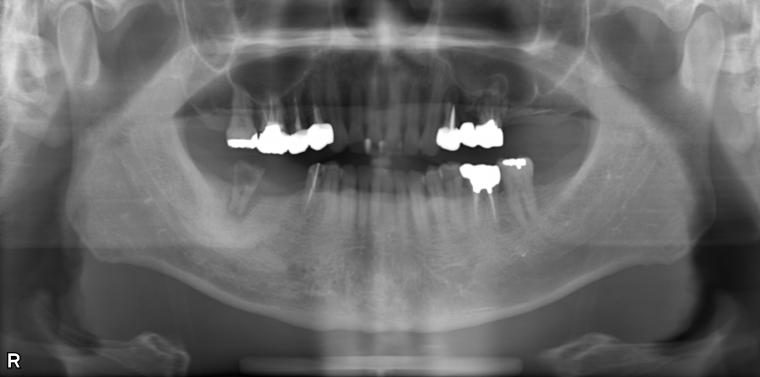

BEFORE

41歳男性/上5本欠損/インプラント埋込手術

上5本が虫歯になってしまった為治療をすることになった患者さんです。

虫歯が進行していて、歯を保存出来なかったため歯を抜いて人工の骨を足してからインプラントを

5本埋込した患者さんです。